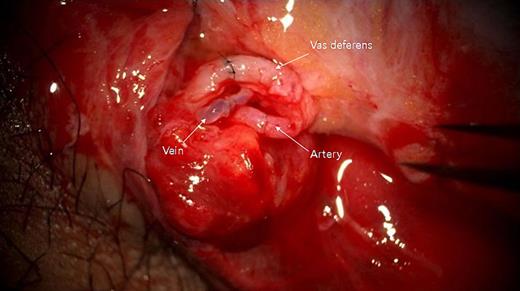

Immediate post-anastomosis findings of the right testis. Upper: vas deferens; middle: testicular vein; lower: testicular artery.